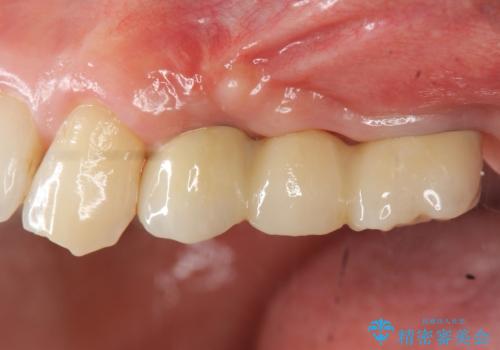

しっかりと造骨を行ったことでインプラント周囲には十分な量の骨が存在し安定したインプラント周囲環境を整えることができました。

最終的なジルコニアクラウン装着後は、まるで自分の歯のように咬める、と咬合機能の回復を大変喜んでいただくことができました。